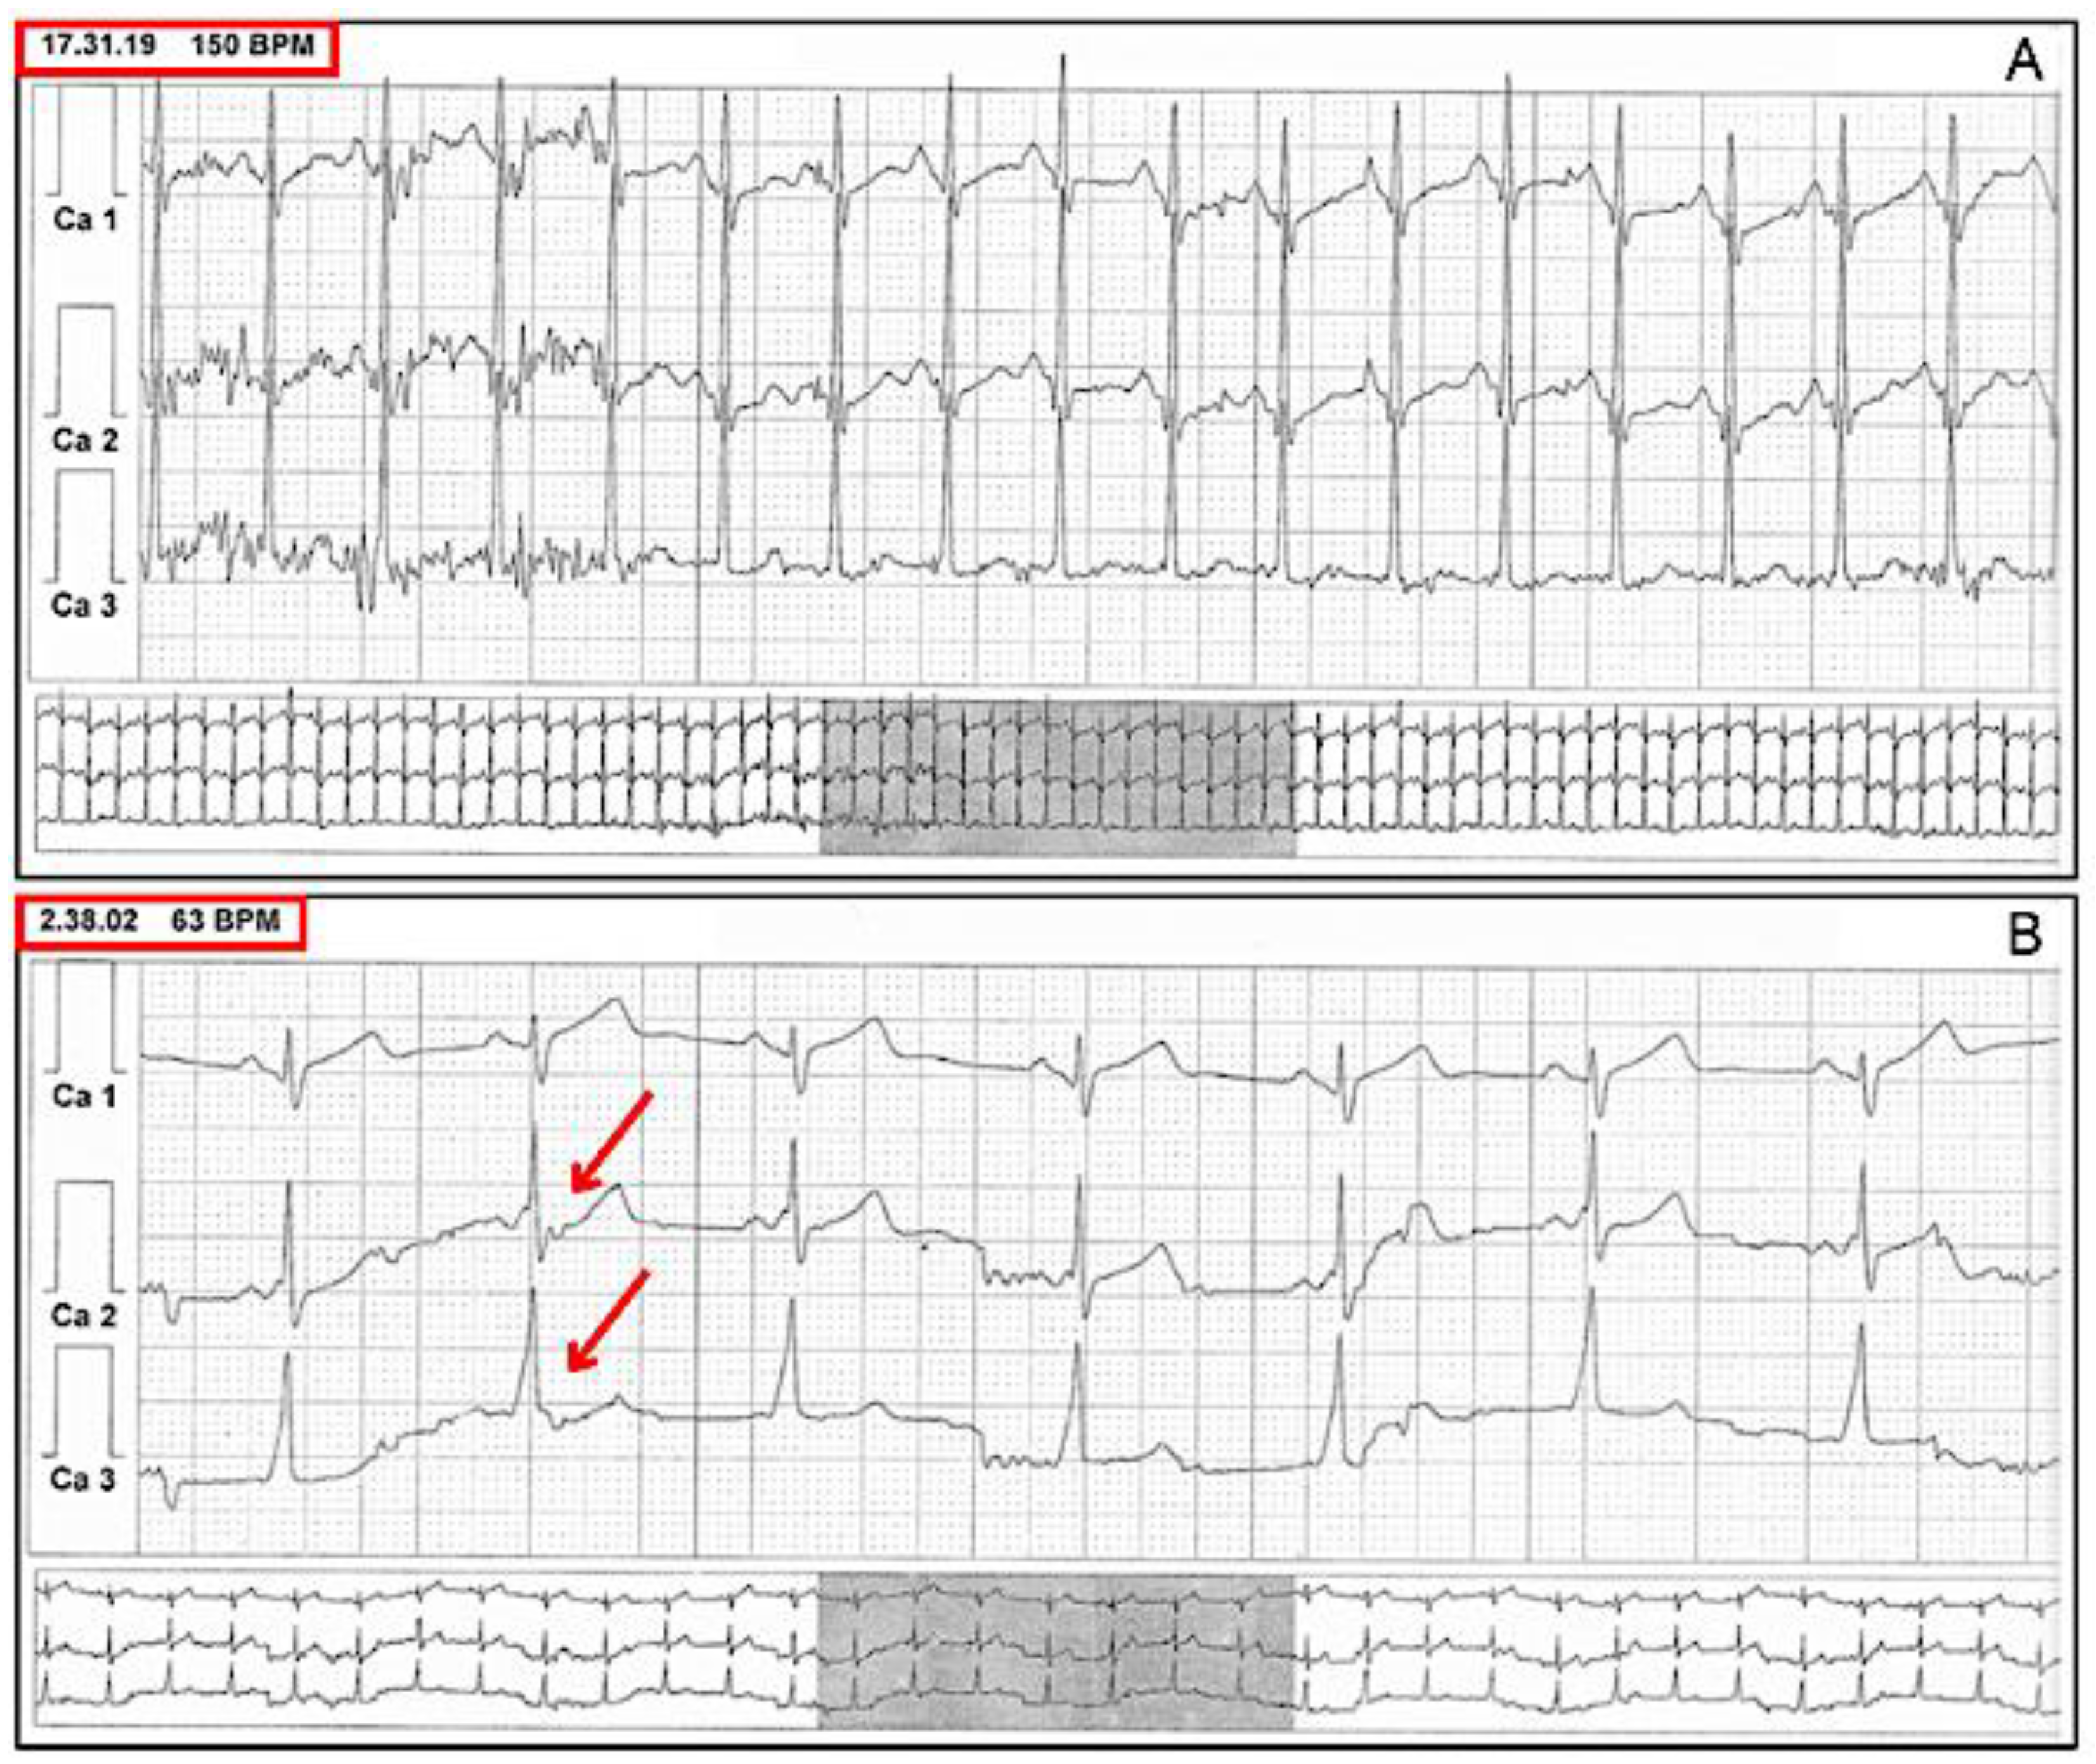

6. Risk Stratification

7. Stress Test Pitfalls